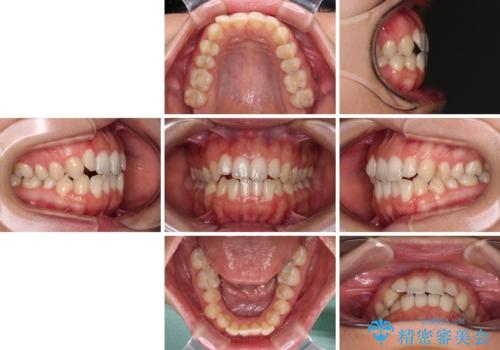

- 前歯の開咬を気にして来院された患者様です。

開咬の治療は、前歯を閉じるように動かすとともに、上下臼歯を圧下(骨内にめり込ませる)させることで進めて行きます。

インビザラインは臼歯の圧下を効果的に行えるため、インビザラインを用いて矯正治療を行うこととしました。

オープンバイトは舌の突出癖により誘発され、治療後も突出癖が残っている容易に後戻りしてしまいます。

治療期間を短縮するためにも、舌突出癖の改善が極めて重要となります。